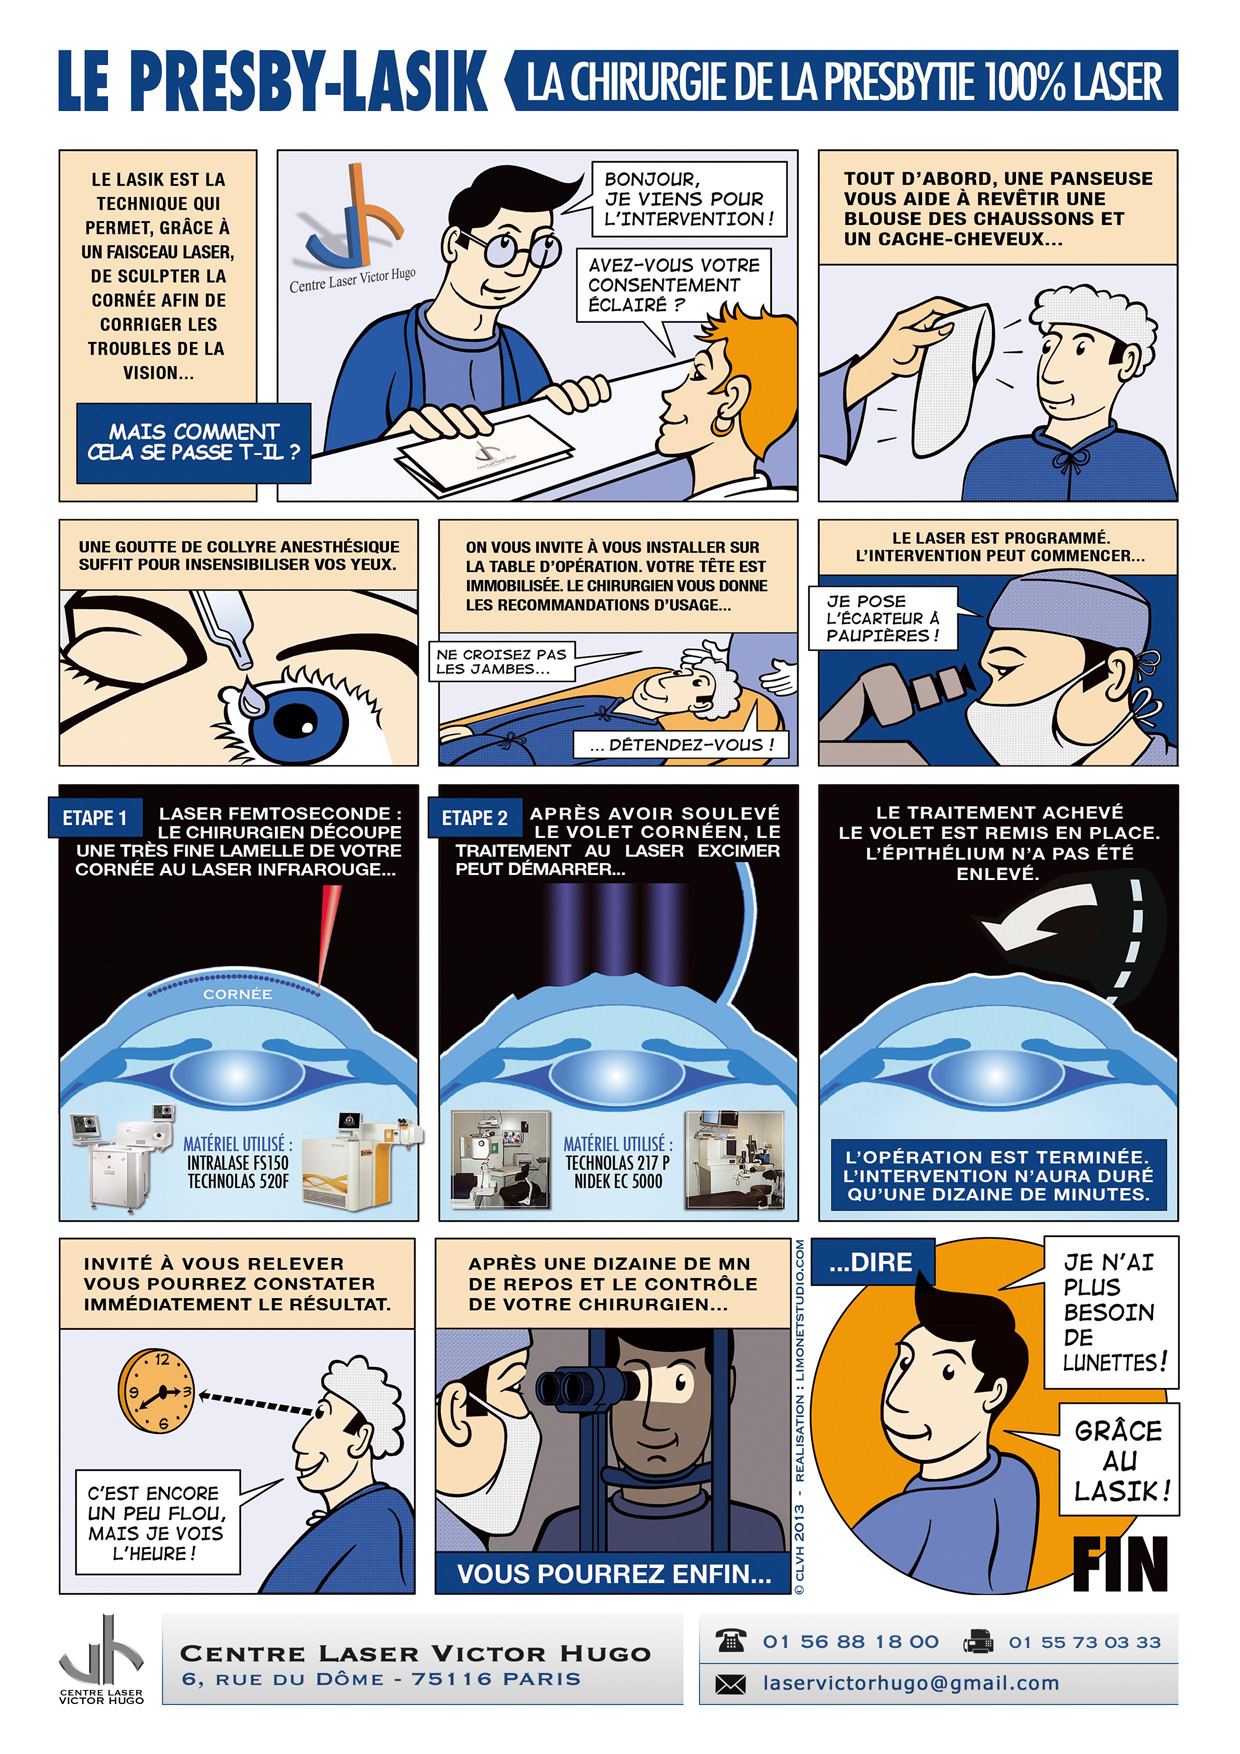

Afin de répondre aux interrogations d'un public de plus en plus intéressé, nous vous proposons cet ouvrage explicatif sous la forme d'une bande dessinée ludique. Cette bédé aborde les troubles de la vision, la chirurgie réfractive (LASIK, PKR et PresbyLASIK), la technique des anneaux et des implants. Cette bébé aborde également l'amblyopie et son traitement orthoptique. Maintenant... à vous de voir !